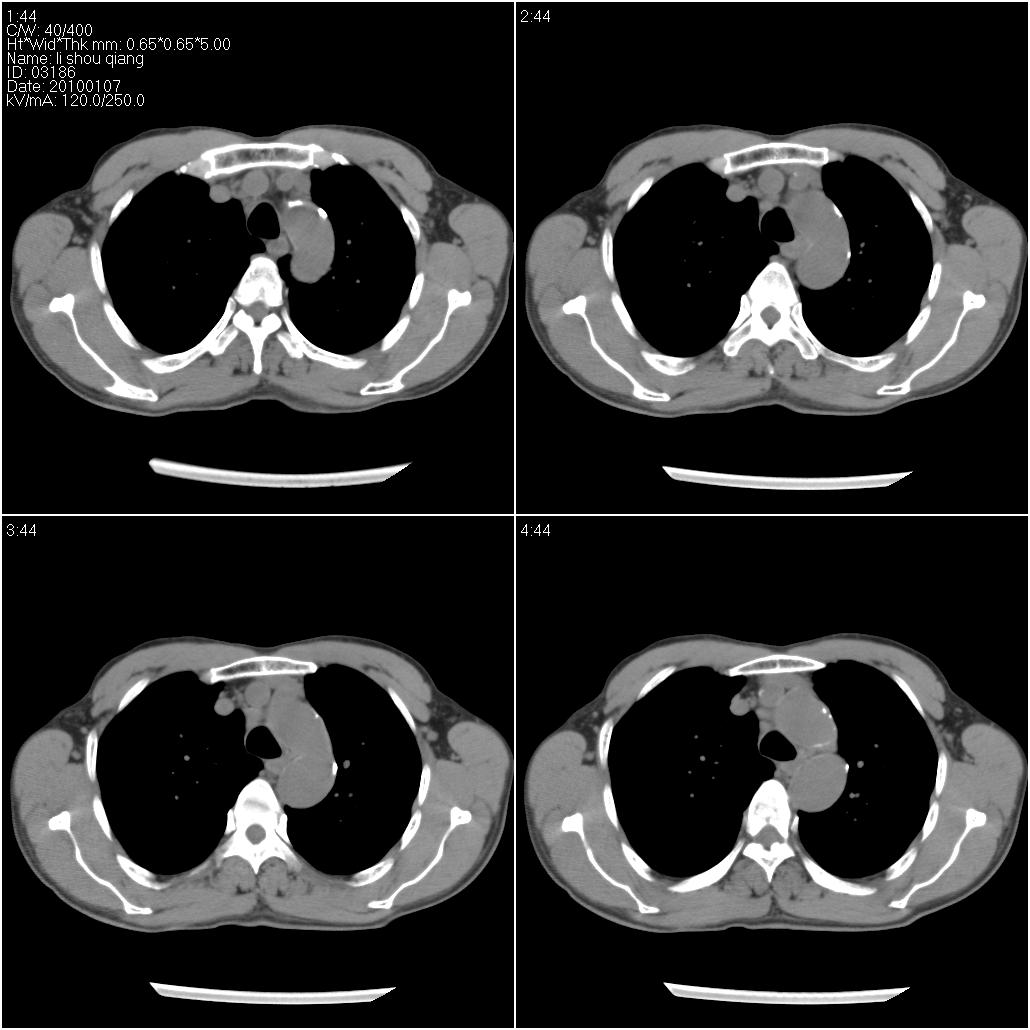

标题: CT24038:男性,58岁。主因咳嗽带血性CT检查。 [打印本页]

标题: CT24038:男性,58岁。主因咳嗽带血性CT检查。

右肺中叶外侧段见一不规则的软组织肿块,边缘可见毛刺,并见厚壁空洞,与胸膜分界欠清。另左下肺见多个小囊状扩张区

右肺中叶外侧段可见团块影,外形不规则,内见空泡征。左下肺见蜂窝状低密度透亮影,部分层面主动脉旁瘤样突出。考虑右肺中叶外围型肺癌可能性大,左下肺支气管扩张,主动脉弓瘤样突出。